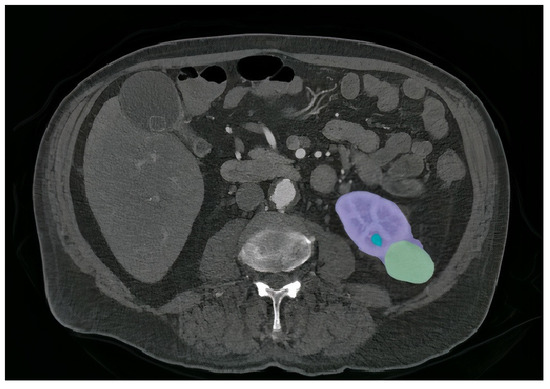

4.4. Incorporating GCAM-Attention Fusion to UNet-PWP on CT Scan